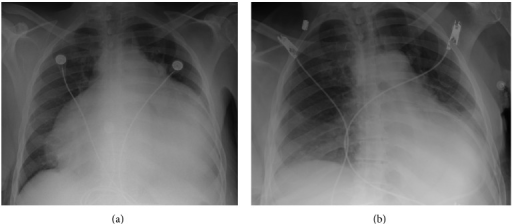

Histopathology of (a) normal myocardium and (b) myocardial hypertrophy. Scale bar indicates 50 μm.

a) Cardiomegaly due to pericardial fluid b)after pericardial fluid drainage.